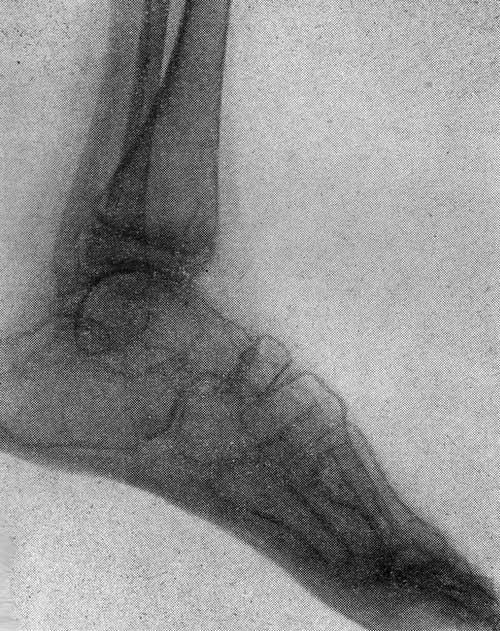

Выраженный системный остеропороз костей голеней

и стоп («стеклянные кости»)